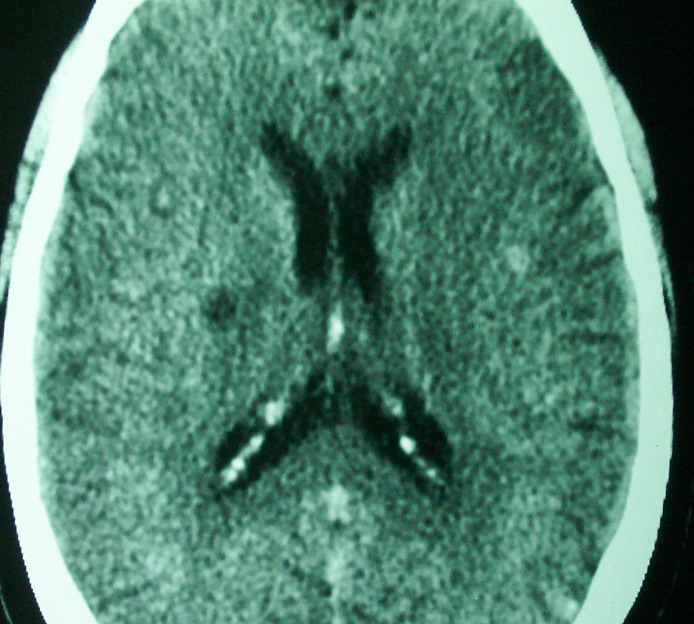

标题: CT18022:颅内多发稍高密度影 [打印本页]

标题: CT18022:颅内多发稍高密度影

f     60    左侧肢体活动无力3天余,    神志情,  无抽搐史   无发热   否认囊虫接触史

有囊有节有钙化,这个表现符合混合型脑囊虫病.请结合临床资料并进行补体结合试验.

有囊有节有钙化,考虑混合型脑囊虫病.